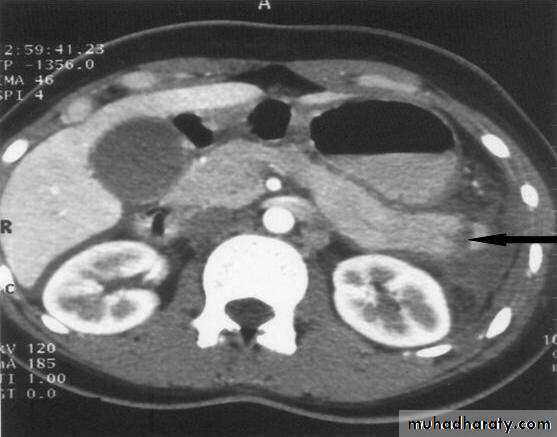

Radiology of acute pancreatitis

U/S

useful for biliary pathology, 70-80% sensitive for pancreatitisCT more useful for judging severity and regional effects